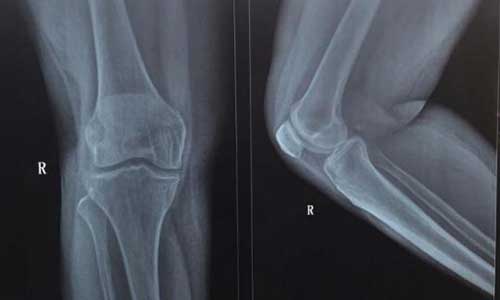

(图:X光示 患者双侧膝有炎性症状,行走时不便)

DR检查:左侧肘关节退行性改变,双侧膝关节骨关节炎改变

HD-热层析检测系统检查:患者双膝和双踝关节处均有大量炎性症状产生,双膝病情发展有加重趋势。